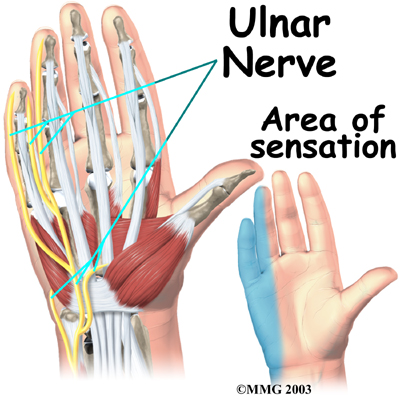

All of the nerves that travel to the hand and fingers begin together at the shoulder: the radial nerve, the median nerve, and the ulnar nerve. These nerves carry signals from the brain to the muscles that move the arm, hand, fingers, and thumb. The nerves also carry signals back to the brain about sensations such as touch, pain, and temperature.

The travels through a separate tunnel, called Guyon's canal. This tunnel is formed by two carpal bones, the pisiform and hamate, and the ligament that connects them. After passing through the canal, the ulnar nerve branches out to supply feeling to the little finger and half the ring finger. Branches of this nerve also supply the small muscles in the palm and the muscle that pulls the thumb toward the palm.